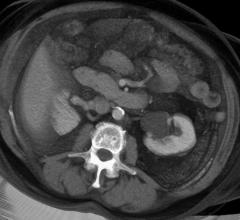

Contrast media, also called contrast agents, are used to enhance the blood and perfusion in tissues. This includes iodine based contrast for on computed tomography (CT), gadolinium based agents for MRI and lipid bubble contrast agents used in ultrasound.

Contrast agents improve every kind of medical image from computed tomography (CT) to magnetic resonance imaging (MR) ...

The medical imaging market relies heavily on contrast media, injected into patients to increase the contrast of bodily ...